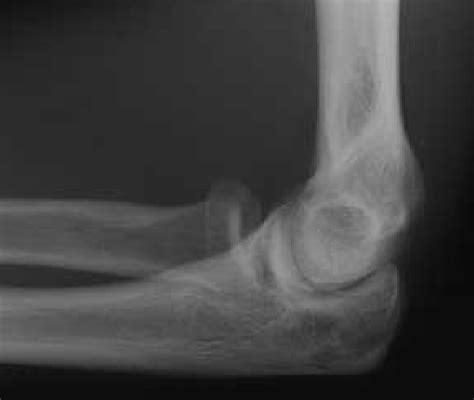

The diagnosis of moderate joint effusion typically involves a combination of physical examination, imaging studies, and laboratory tests. Physical examination may reveal joint swelling, warmth, and limited mobility, while imaging studies such as X-rays, ultrasound, or magnetic resonance imaging (MRI) can help confirm the presence of excess fluid within the joint space. Laboratory tests, including complete blood count, erythrocyte sedimentation rate, and C-reactive protein, can help identify underlying inflammatory or infectious conditions.